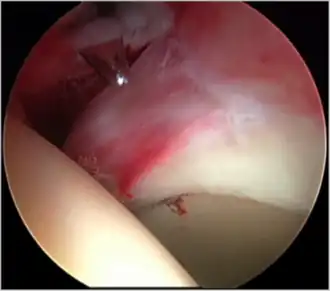

Figure 5. Portal placement under direct vision. The instrument is entering the joint through the hip capsule, between the femoral head (on the left) and acetabular labrum (on the right)

The next step is to insert a fine needle under x-ray guidance into the hip joint. This breaks the 'suction seal' of the joint and allows further distraction if necessary (see fig 4). The surgeon wishes to see the ball move out the socket by approximately 1 cm, so that access to the hip joint can be achieved with minimal risk of damage to the joint surfaces. Most surgeons will inject fluid into the joint at this stage, again to ensure that there is enough space between the ball and socket for safe instrument access. This needle is then removed. The next step is placement of the 'portals', or the small holes made to pass instruments into the joint. This is achieved by again passing a fresh hollow needle into the joint under x-ray control, usually in a slightly different position. The reason for this is so the surgeon can ensure that the needle, and subsequent cannulae do not penetrate and damage the acetabular labrum or cartilage joint surfaces (see fig. 5). Again, surgeons will have their own preferences as to their preferred placement. Through this hollow needle, a long thin flexible guide wire is passed into the joint, and the needle is removed over it, leaving the guide wire in situ. A small cut in the skin is made around the wire, to allow for larger cannulae to be placed over the wire through the portal. The wire therefore guides the larger cannulae into the joint. The most common external diameters of cannulae used are between 4.5 and 5.5 mm. Once the surgeon is satisfied that the cannula is in the correct position, by a combination of feel and x-ray guidance, the guide wire can be withdrawn. Once the first portal is correctly placed, any further portals may be created once the camera is in position, to ensure that they are placed with minimal risk to the joint surfaces. This process can be repeated to gain as many points of entry to the hip joint as the surgeon requires, normally between two and four. Certain of these entry points will be used for the viewing arthroscope and others for operating instruments.